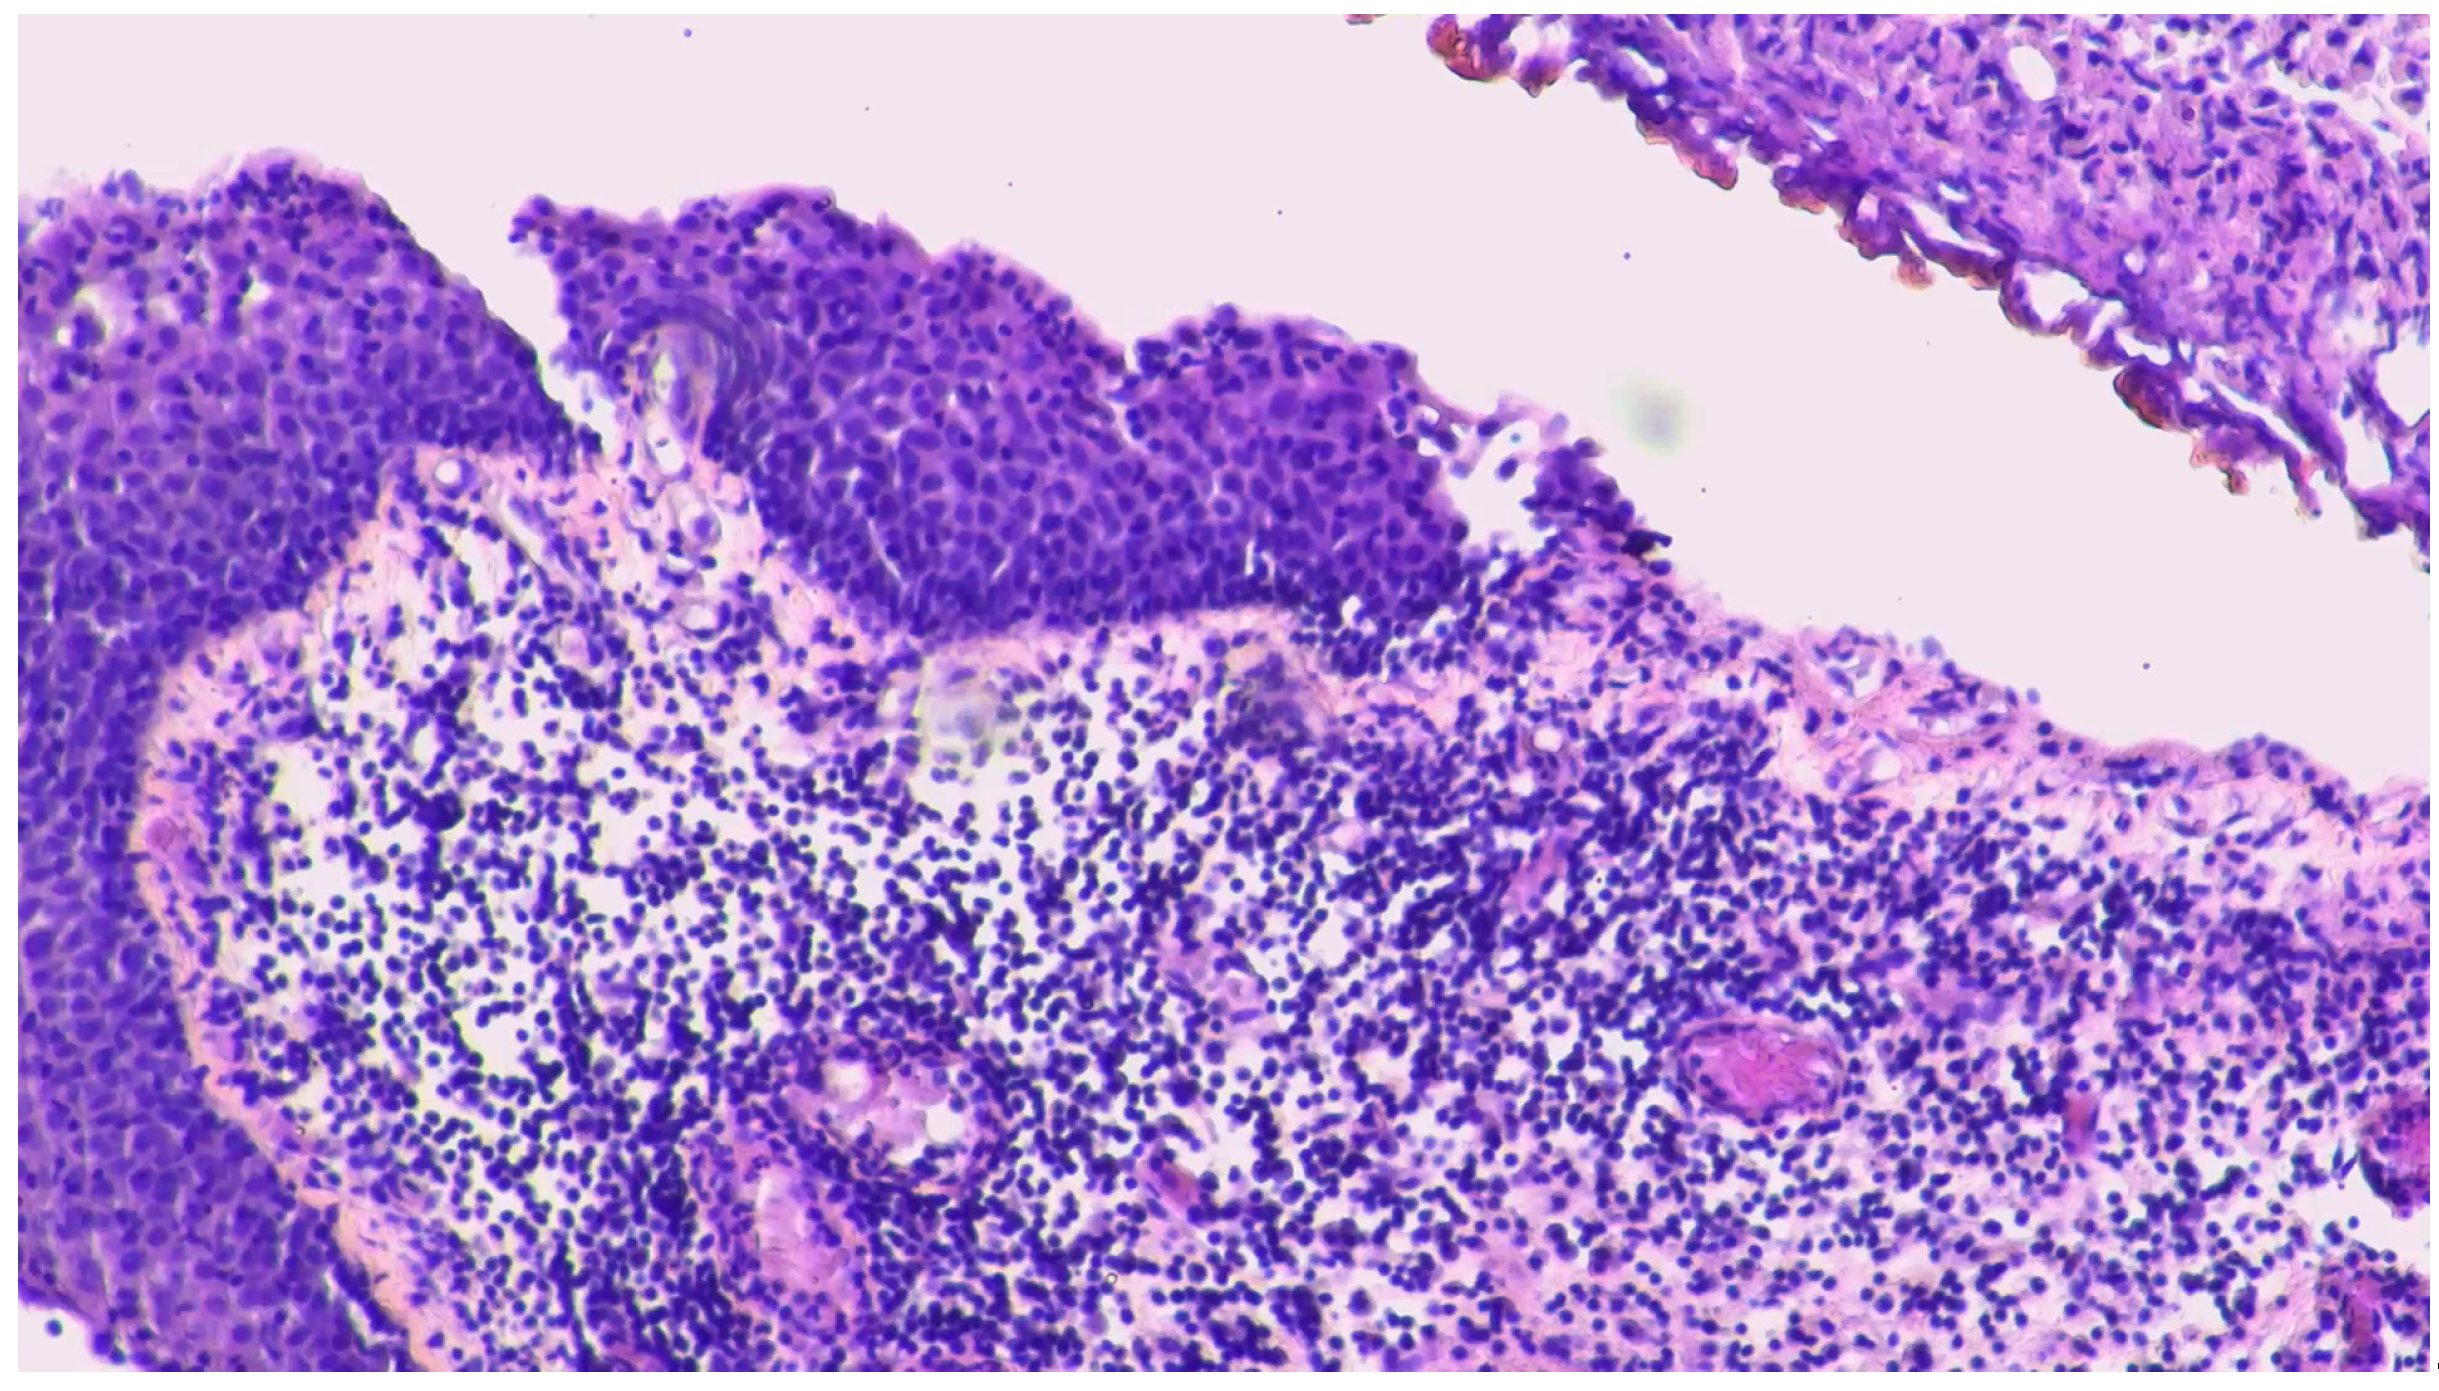

Magnetic resonance (MRI) of the brain was performed, reporting the presence of 3 brain lesions (one in the left frontal lobe of about 4 cm, the other 2 in the cerebellum right and left of about 2 cm) with oedema (Figure 1a-b-c). Moreover, an occipital bone lesion was reported.

Figure 1. Brain magnetic resonance at diagnosis. Legend: (a) right cerebellar lesion; (b) left cerebellar lesion; (c) left frontal lobe lesion.